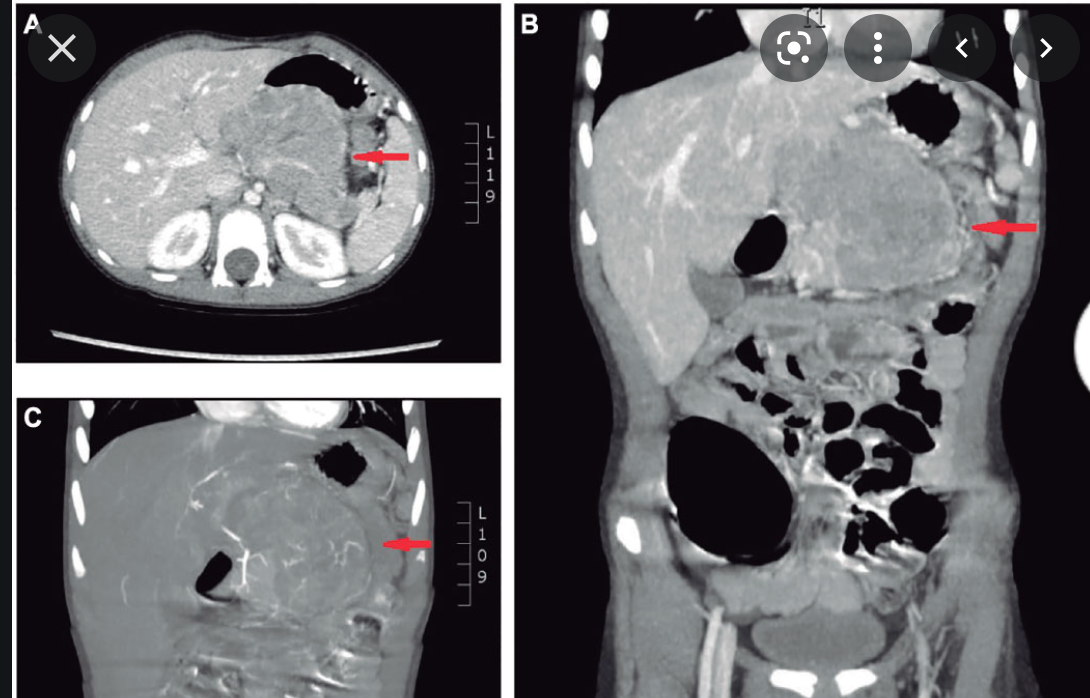

Findings: A well-defined rounded exophytic cystic lesion measuring 6.3 x 7 x 7 cm is seen originating from the tail of the pancreas. It has an average density of 8 HU and shows mild peripheral enhancement on post contrast study. A few thin septations and a tiny mural calcification are seen in it. No solid component is seen in it. Morphology of the remaining pancreas is unremarkable.

Impression: Well-defined rounded exophytic cystic lesion originating from the tail of the pancreas, which is likely, a mucinous cystadenoma of the pancreas (mucinous cystic neoplasm of the pancreas) with possible differential diagnosis of pancreatic pseudocyst (if there is a past history of pancreatitis). Another possible differential can be a hydatid cyst which is however, very unlikely.